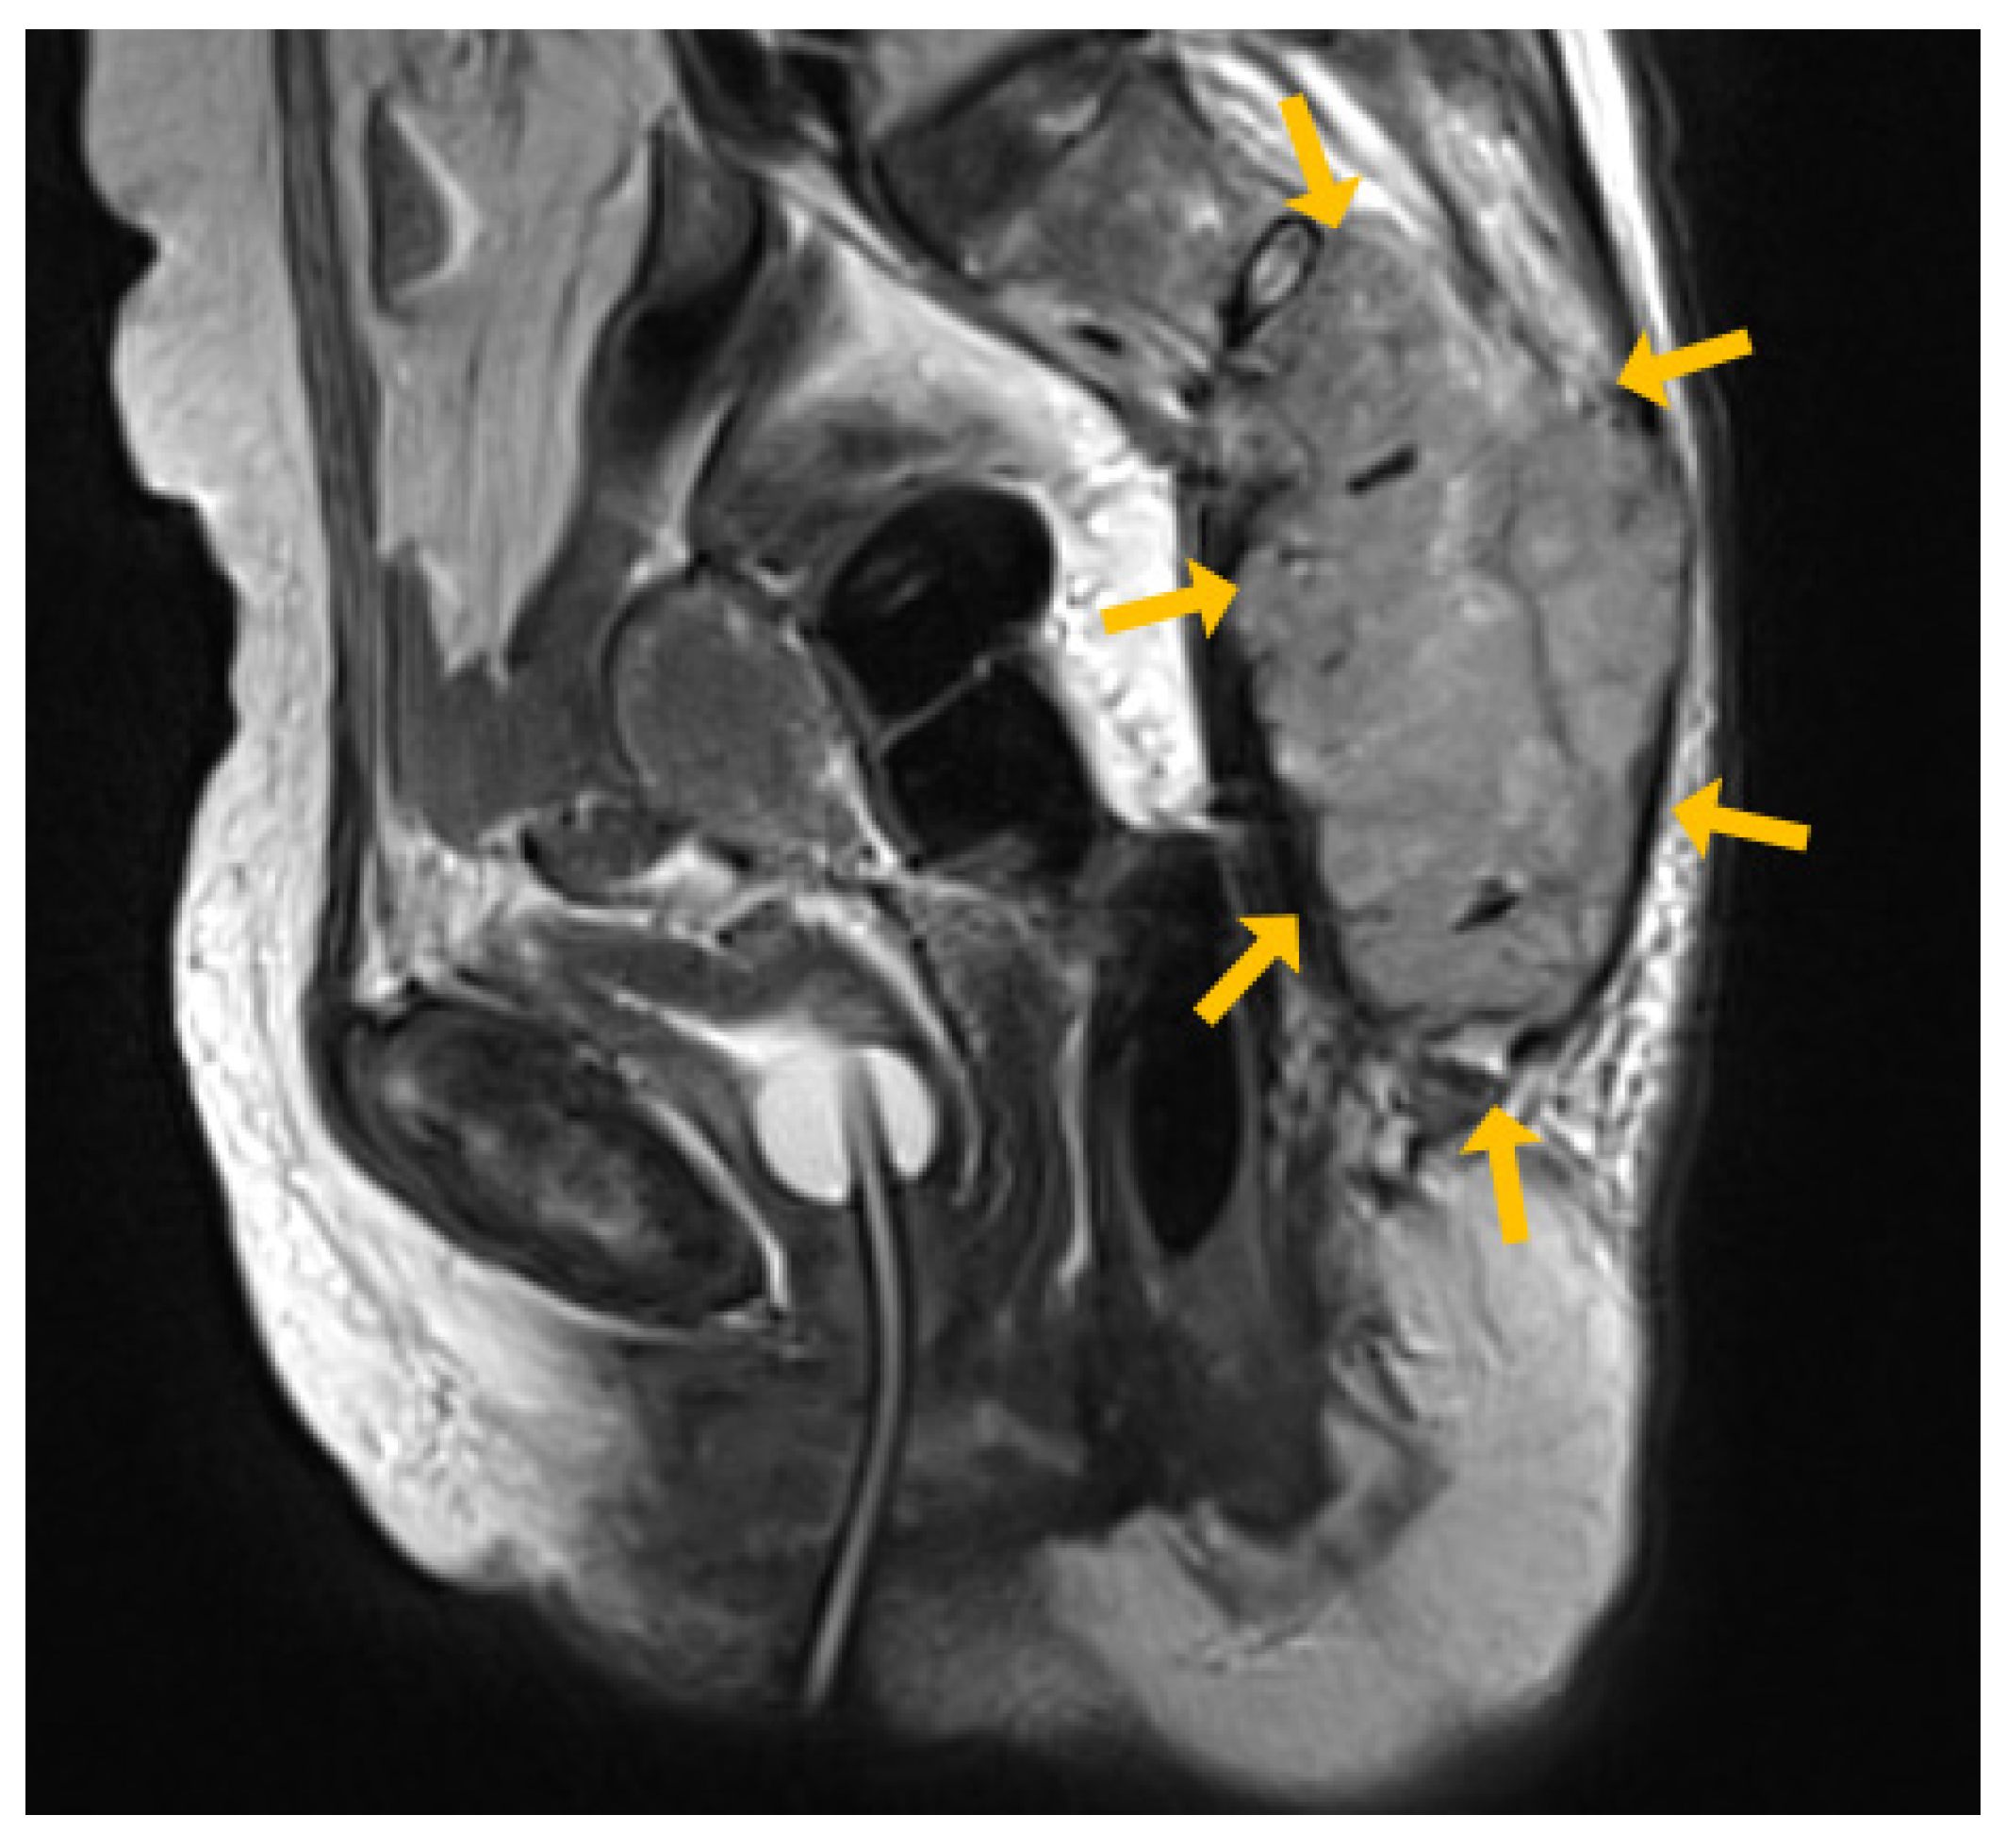

2. Case Report